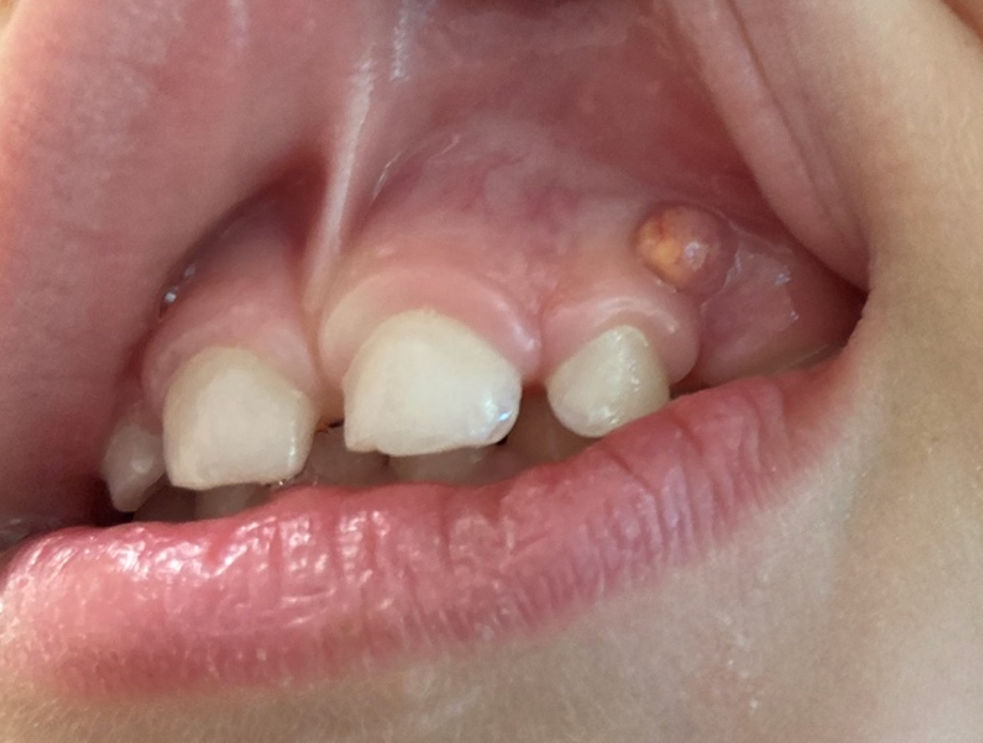

25-month-old boy with palatal lesion

A 25-month-old boy with a palatal lesion.